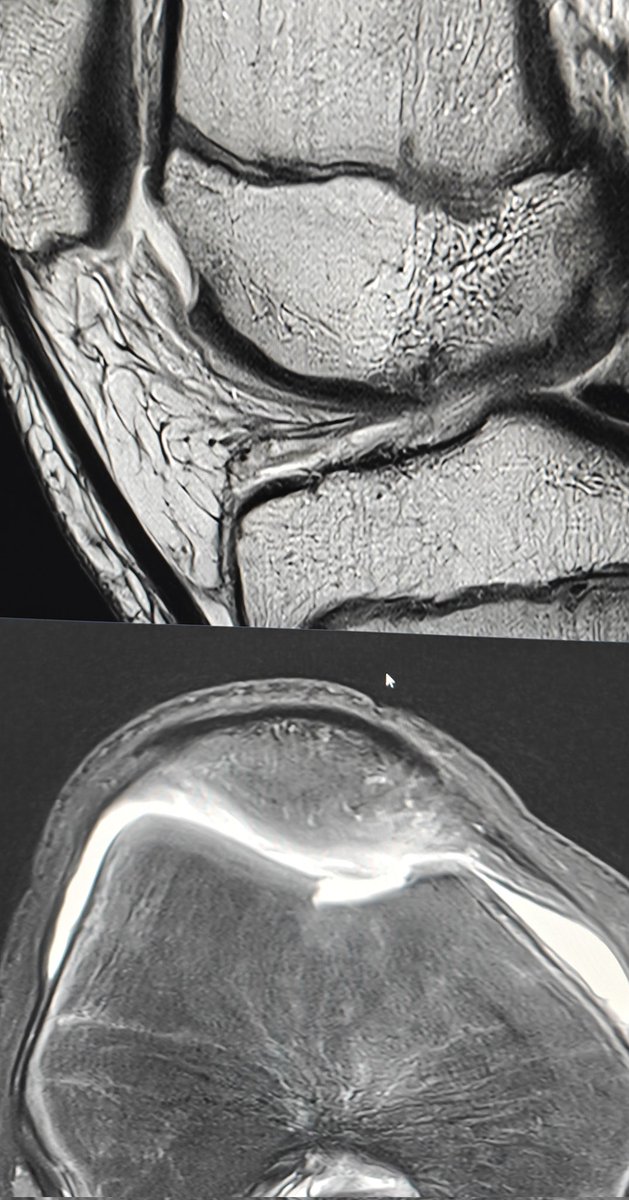

•Adolescent - acute chondral fracture trochlear. •Sharp edges give it away. •Maybe have been chondral delamination before 🤔 •Displaced fragment within the lateral gutter. #mskrad #foamrad

Neeraj Purohit tweet mediaNeeraj Purohit tweet mediaNeeraj Purohit tweet media